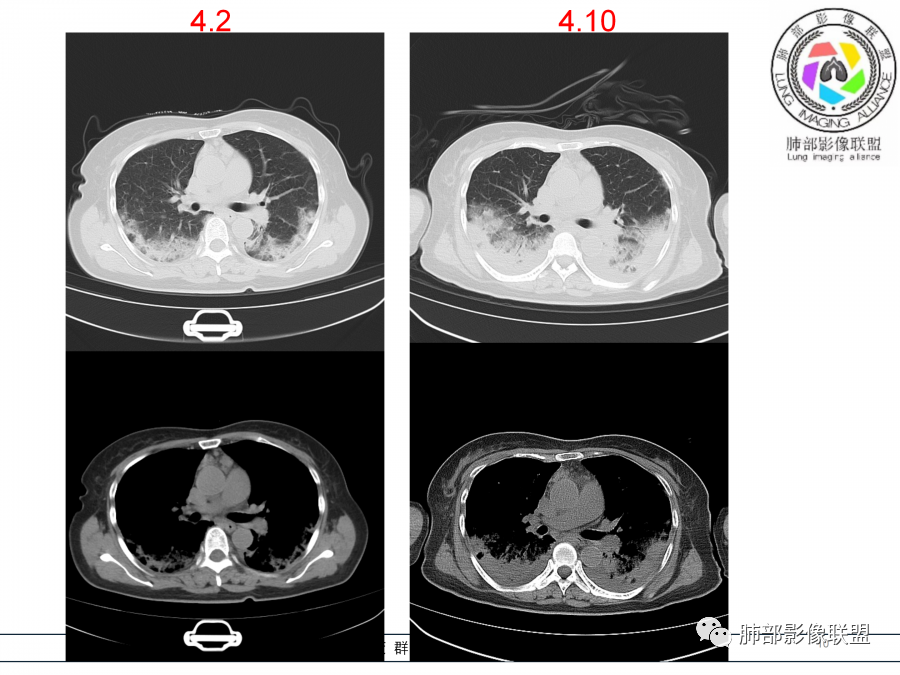

影像,第一次双肺中下叶胸膜下多发斑片状实变影,部分融合成,周围散发磨玻璃影,磨玻璃影内可见小叶间隔及小叶内间隔增厚,病变平行于胸膜,第二次间隔8天,双肺实变影明显进展,有重力作用,支气管近端堵塞,进展较快,临床有发热,血沉高,狼疮SLE阳性,考虑1:OP(机化性肺炎)2:SLE相关肺炎,建议支气管镜灌洗液病原学检测。

老年女性,咳嗽咳痰伴发热7天,白细胞不高,血沉快,降钙素原不高。其他化验未见明显异常,狼疮全套抗Ro/SSA阳性,双肺野靠近胸膜下磨玻璃实变影,支气管通畅,有充气征,沿胸膜下分布,有细网格征,7天后进展明显,实变影加重,胸膜肥厚,胸水不明显,心包少量积液?抗感染治疗无效,考虑非感染性疾病可能性大,结缔组织相关性肺病?狼疮性肺炎?机化性肺炎?鉴别病毒性肺炎。

老年女性,咳嗽咳痰发热7天。无气促。白细胞计数不高,PCT稍高,PPD(+),抗Ro/SSA阳性。CT:双肺野靠近胸膜下磨玻璃实变影,支气管通畅,有充气征,沿胸膜下分布,有细网格征。予抗生素治疗,8天后复查胸部CT见病灶范围扩大,实变影加重,胸膜肥厚,胸水不明显。抗感染治疗无效,考虑有:1.非感染性疾病:结缔组织相关性肺病,支持点:肺部CT表现为间质性炎症病变,抗RO/SSA(52)阳性;2.病毒性肺炎:患者无气促症状,可能性小;3.肺结核。

第一次双肺中下叶胸膜下多发斑片状磨玻璃及实变影,病变平行于胸膜,支气管通畅,8天后,双肺实变影明显进展范围扩大,部分支气管近端堵塞,进展较快,胸腔积液,抗感染治疗无效,考虑:非感染性疾病:结缔组织相关性肺病。鉴别机化性肺炎。

外围胸膜下,实变+GGO+网格,支气管通畅

提示间质为主病变